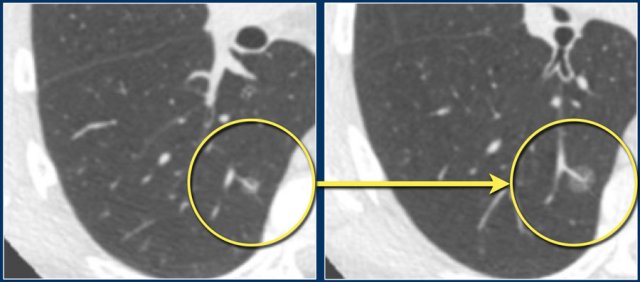

Transient subsolid nodule Transient subsolid nodule

Transient subsolid nodules usually represent infection or alveolar hemorrhage.

To differentiate between transient or persistent subsolid nodules a follow-up CT should be obtained.

Previously, it was recommended to repeat imaging after 3 months, however, this interval has been increased to 12 months.

Because of the slower growth rate, the total follow-up period for persistent subsolid nodules has been increased to 5 years.

The images show a 7 mm pure groundglass subsolid nodule in the right upper lobe.

On follow-up CT this proved to be a transient subsolid nodule.